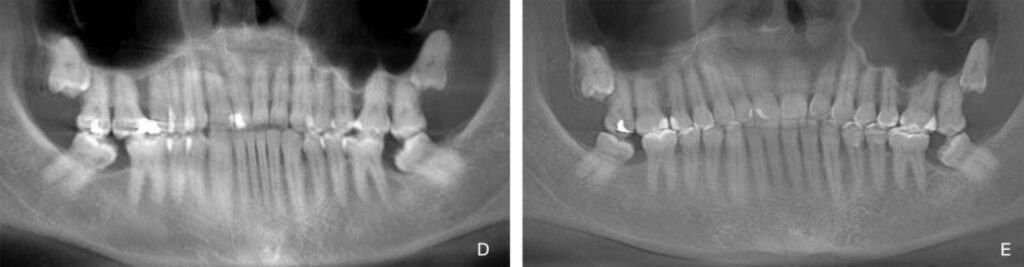

Figure 3. Patient 3. Generalized severe pathological tooth wear (TWES 2.0). (A) Intraoral situation:

deep bite and occlusal relationships shown by a patient with severely worn anterior teeth. (B) Occlusion

after orthodontic and restorative treatment, indicating aesthetic and functional improvement.

Felspathic vestibular veneers from 1.5 to 2.5, CAD-CAM nanoceramic palatal veneers from 1.3 to 2.3,

lithium disilicate veneers from 3.3 to 4.3 and a direct stamped composite resin in the posteroinferior

sectors (3.4–3.6 and 4.4–4.6). (C) A 5-year follow-up photograph. Note the maintenance of occlusal

contact relationships. (D) Initial orthopantomography. (E) Final orthopantomography showing the

supplementation of all teeth with an endodontic treatment in 1.4 due to previous necrosis.